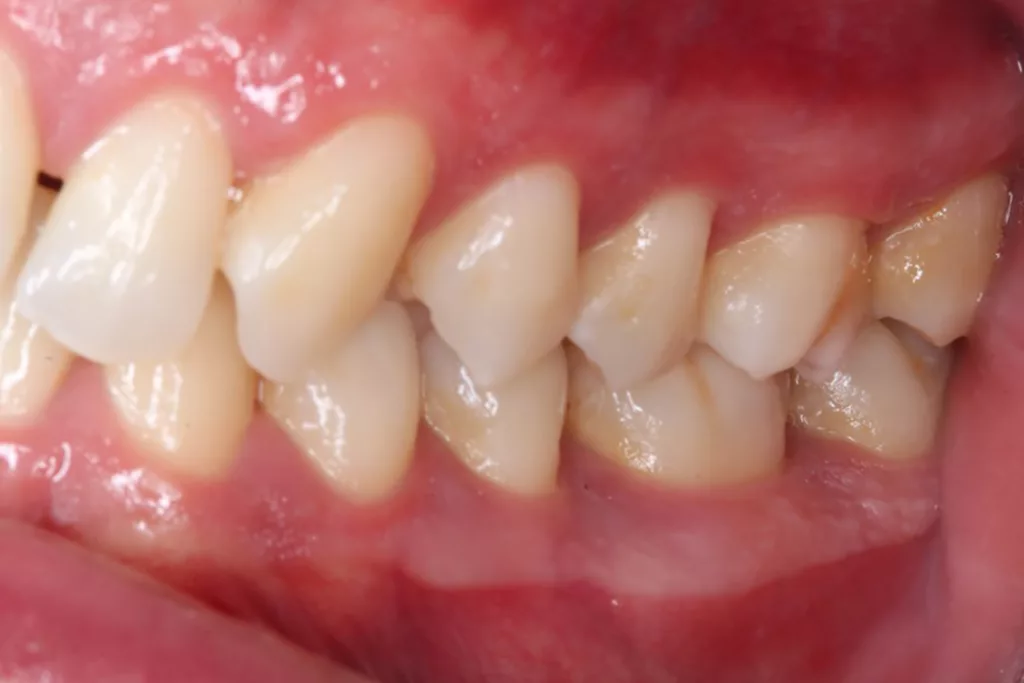

Robuste Evidenz aus aktuellen großen bevölkerungsbasierten Studien zeigt eine Überlegenheit der Effektivität elektrischer Zahnbürsten gegenüber Handzahnbürsten. Darüber hinaus legen systematische Übersichtsarbeiten und In-vitro-Studien einen zusätzlichen Effekt – die Putzwirkung auch ohne direkten Borstenkontakt durch unterschiedliche Strömungsphänomene – bestimmter elektrischer Zahnbürsten (Schallzahnbürsten) nahe. Laboruntersuchungen zeigen aber auch große Unterschiede der untersuchten Zahnbürsten hinsichtlich der Effektivität der Biofilmreduktion. Das bedeutet, dass in der Klinik (Abb. 7–9) in aller Regel eine Empfehlung für elektrische Zahnbürsten und (!) geeignete Hilfsmittel für die Zahnzwischenraumpflege vorliegen sollte.